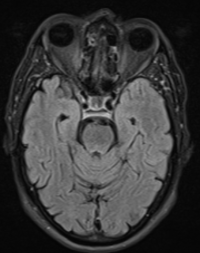

Series 001 — Frontal Lobe Mass (Likely Meningioma) Overview

Initial scan set with key anatomical landmarks and first-pass observations.